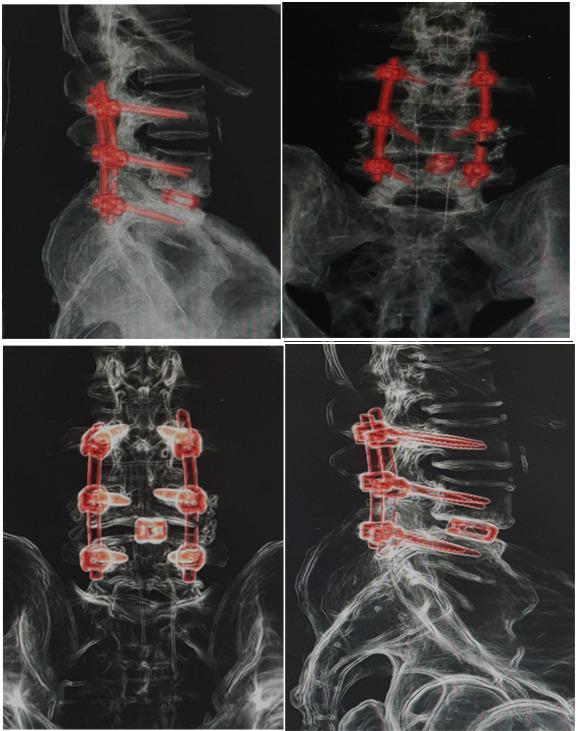

وقد تكللت العملية ولله الحمد بالنجاح- وتمكّن المريض ولأول مرة منذ عامين المشي والحركة بدون ألم أو تنميل في الأطراف السفلية، حيث تم خلال العملية تثبيت الفقرات القطنية بواسطة مسامير تيتانيوم مع تركيب قفص تيتانيوم (إلمانية الصنع)، بهدف رفع الضغط عن جذور الأعصاب وتوسيع القناة العصبية القطنية وتوسيع مخارج جذور الأعصاب.